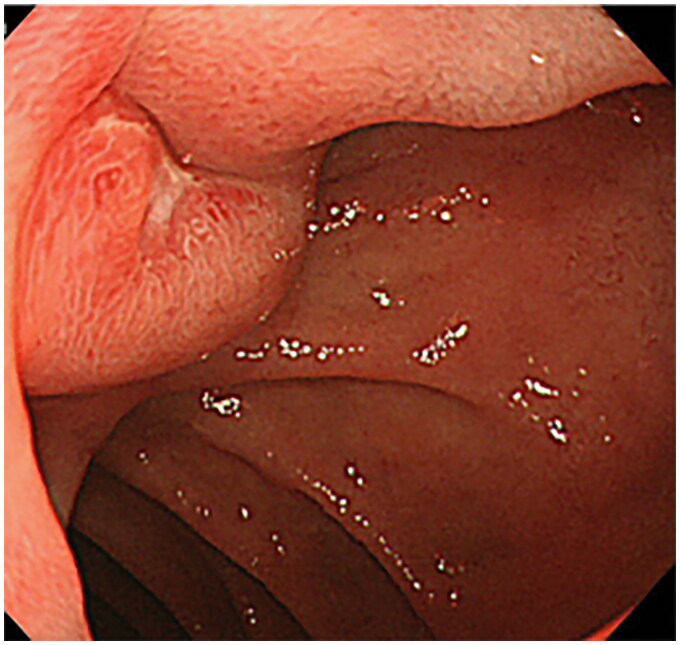

Duodenal bulb adenocarcinoma is a rare malignancy of the gastrointestinal tract. This cancer often presents with an insidious onset, making it challenging to diagnose early. A noteworthy case-study involved a 56 year-old-woman complaining from epigastric transfixing pain, jaundice, and overall health decline. The initial diagnosis suspected was a pancreatic tumor. An abdominal CT scan however showed no abnormality in the pancreas but revealed on the other hand an irregular, non-stenosing, heterogeneous fibrous thickening of the lower aspect of the duodenal bulb. An EGD showed a congested infiltrated area in the post-bulbar region, and Pathological exam confirmed the diagnosis of a primary adenocarcinoma of the duodenal bulb. The purpose of this article is to present the case of a primary adenocarcinoma of duodenal bulb mimicking a pancreatic tumor: a rare presentation of a rare tumor itself and to present points differentiating these two neoplasms. Diagnosis relies on a comprehensive assessment involving clinical, radiological, endoscopic, and histologic features. Integration of advanced imaging modalities, such as CT/MRI, coupled with upper gastrointestinal endoscopy, is crucial for accurate evaluation.